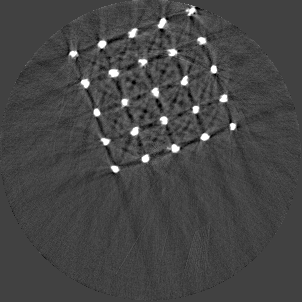

Beam hardening and metal artefacts pose challenges during CT imaging in the presence of metal hardware [17]. This paper presents data that demonstrates the use of spectral imaging in reducing beam hardening effects and metal artefacts. A high-Z sensor layer like CdTe is necessary to provide improved spectral resolution at higher x-ray energies needed for typical implant visualisation. Multi-energy acquisition of metal samples has the added advantage of capturing spectral information which exhibits reduced artefacts and reasonable non-metal (tissue) information. Further, the results were obtained without any hardware filters (except for the intrinsic filter-equivalent in the x-ray tube) and without any numerical corrections. A global reduction in noise due to charge sharing effects was seen due to the availability of CSM. 3D visualisation of the samples (figure 9) revealed finer spatial structures.

Refer to caption

(a) Porous Ti scaffold

(b) Mg scaffold

(c) Ti mesh

Figure 9: High resolution MARS-Exposure Render visualisation of the metal samples